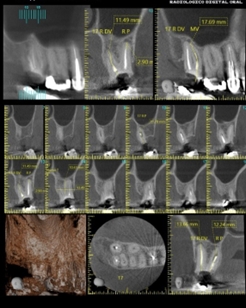

Tratamiento Endodóntico

Antes de iniciar el procedimiento de retratamiento endodóntico, se realiza una evaluación clínica del paciente y se revisa la historia del tratamiento endodóntico previo…

¿Que ventajas presenta el TAC dental?

El dentista podrá hacer en el ordenador cortes bi y tridimensionales de las imágenes que obtiene. Le permitirá observar con detalle cualquier característica de la boca…